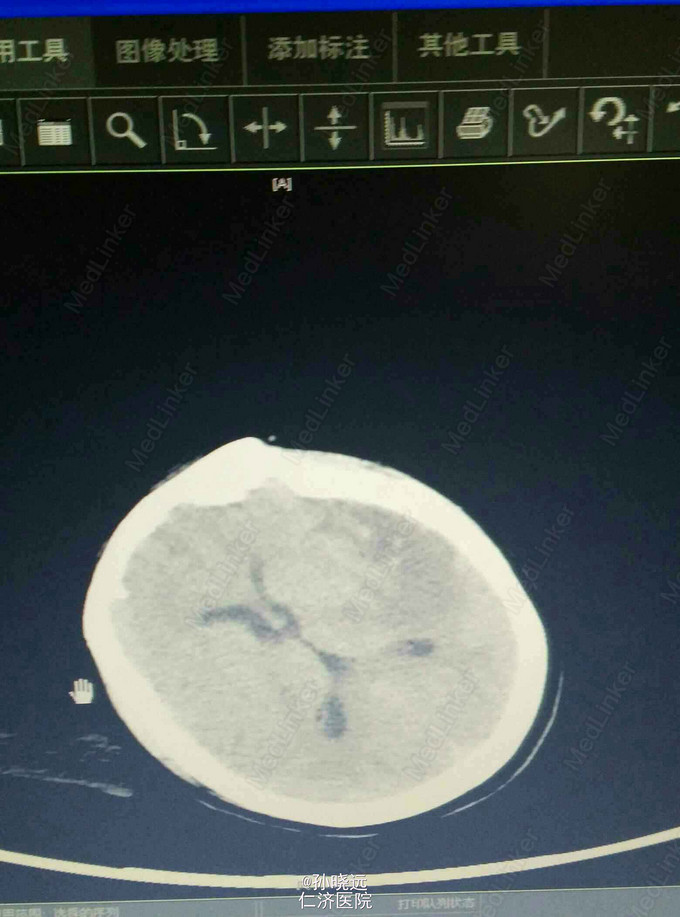

中年女性。主诉:头晕三天,发热伴神志不清1天。 患者于三天前出现持续性头晕,无恶心、呕吐,无视物旋转,来院就诊,查头颅MRI未见异常,予桂哌齐特、长春西汀、硫辛酸治疗,症状无好转。1天前出现高热,最高39.5℃,无咳嗽、气促,再次来院就诊,查血常规:WBC:5.85*10^9/L,N:71.8%,CRP正常,予退热,阿奇霉素等治疗,今日凌晨出现神志不清,无抽搐、恶心、呕吐,头颅CT示两侧颞底部不规则斑点样密度增高影并周围低密度灶,考虑脑炎合并灶性出血,予更昔洛韦、醒脑静、喜炎平、奥美拉唑、甘露醇治疗。后出现氧饱和度下降,予气管插管有创呼吸机辅助通气。 既往史:曾有高血压病史,未应用降压药。

诊断:脑炎。脑出血。 治疗:甲强龙抗炎,更昔洛韦,青霉素钠抗感染,降压,甘露醇、甘油果糖、白蛋白、拖拉塞米里降颅压,呼吸机辅助通气等对症治疗。

腰穿是: 脑脊液生化:葡萄糖:12.18mmol/L,CL:110.9mmol/L,蛋白:222.4mg/dl, 脑脊液常规:淡黄,微混。红细胞:1000*10^6/L,白细胞:1059*10^6/L,潘氏试验阳性(++++),嗜中性粒细胞12%,淋巴细胞:80%,单核细胞8%,凝块无,细菌未找到。 予加用血必净,加强抗感染等治疗。 患者目前仍昏迷,正进行高压氧仓治疗。这是最近一次复查的头颅CT。